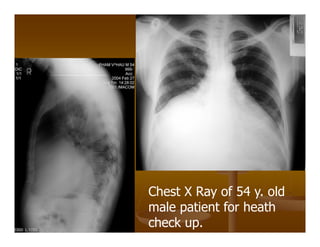

ĐỐ VUI ĐỂ HỌC

Chest X Ray of 54 y. old

male patient for heath

check up.

No dyspnea,no dysphagia

Normal ECG and cardiac US.

CT scan shows

low attenuation

structure around

the heart

Mediastinal

lipomatosis